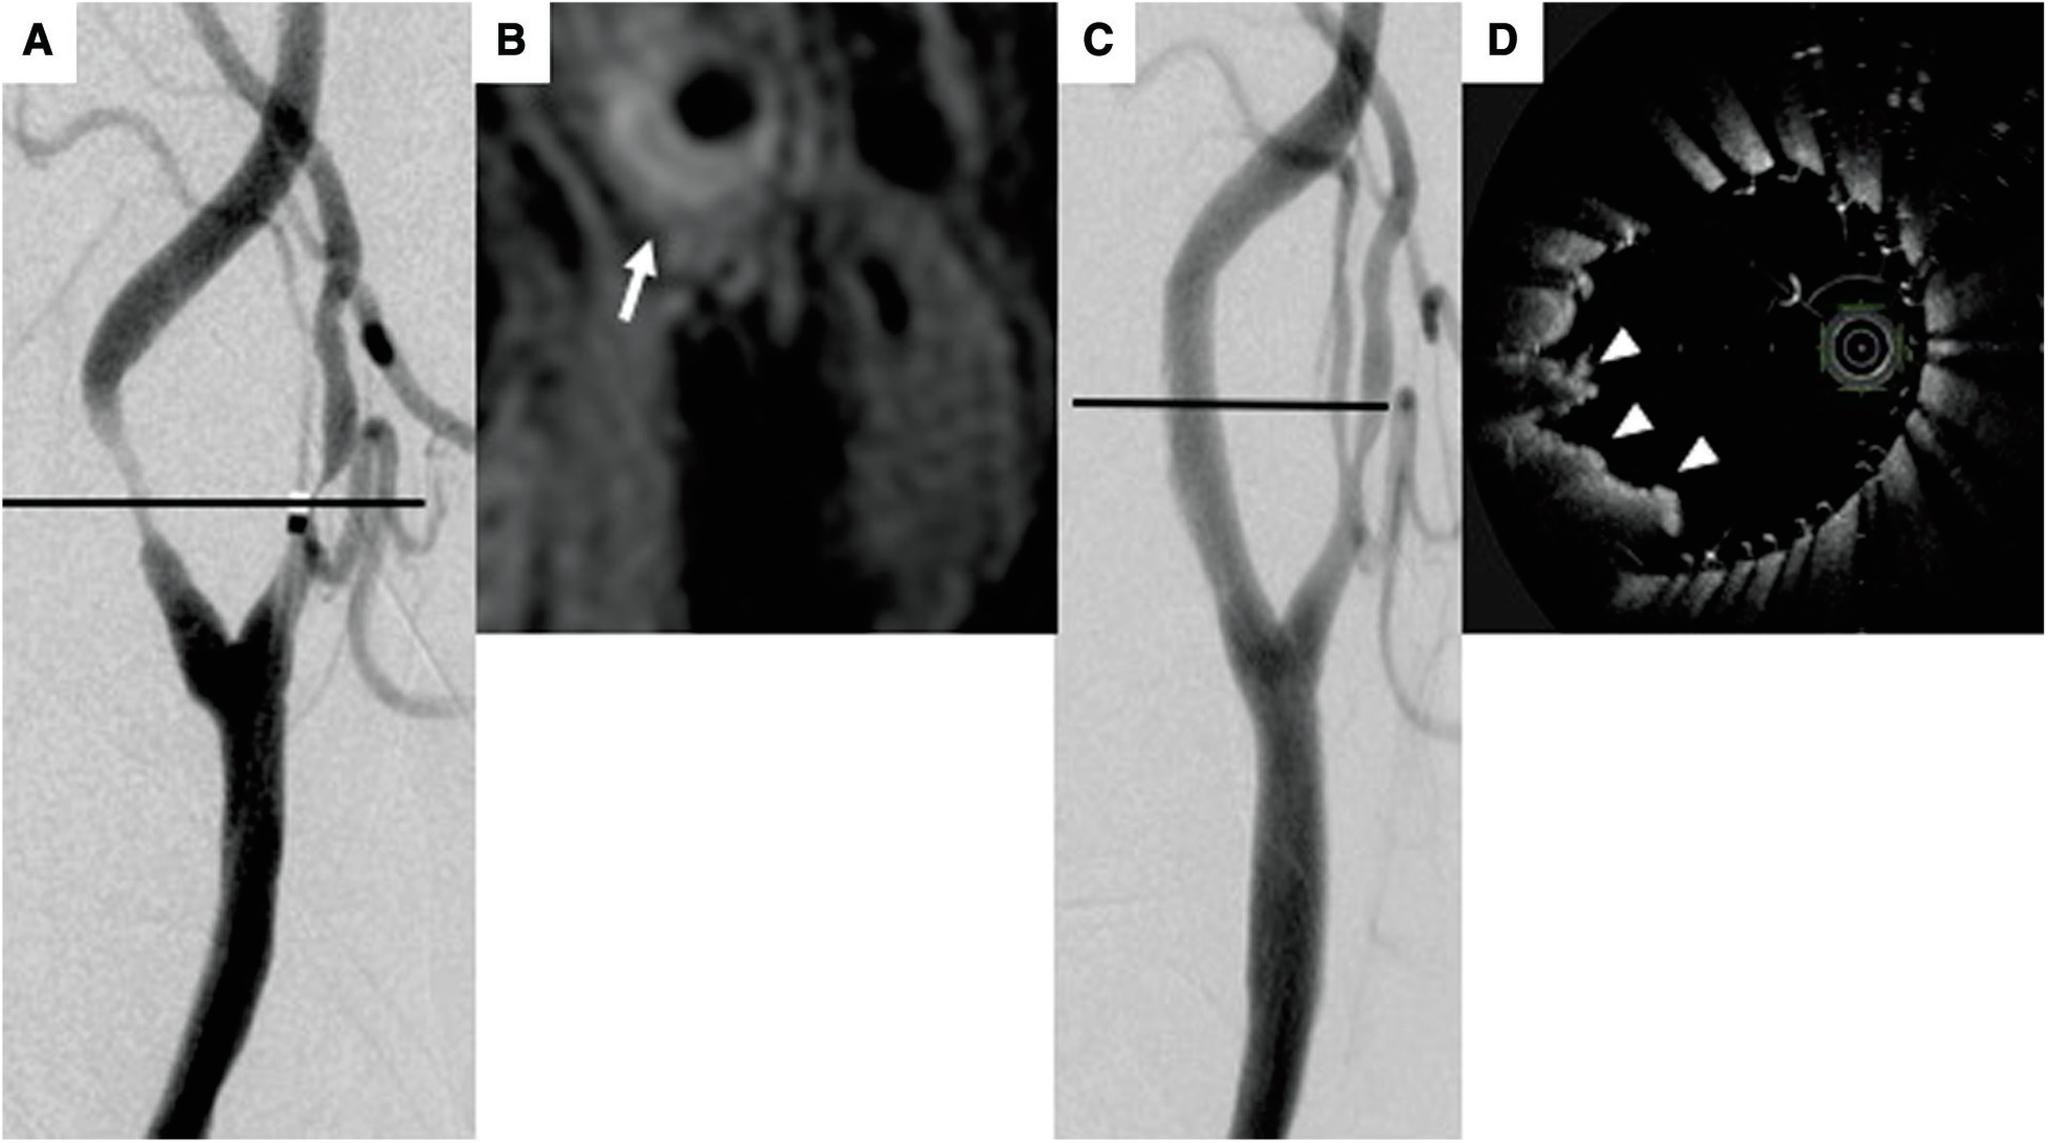

Carotid artery stenting (CAS) has recently emerged as a potential alternative to carotid endarterectomy (CEA) in Japan. However, one of its disadvantages is the higher incidence of ischemic complications than CEA, such as distal embolism during or after the procedure. Plaque protrusion (PP) through the stent strut after deployment of the stent has been suggested as one of the major causes of distal embolism, especially in patients with unstable plaques. The need for increased plaque coverage to reduce the risk of PP through the stent struts has led to the development of a double-layer micromesh stent (micromesh stent) system. This stent system has already been used clinically in European countries with good short- to medium-term follow-up results. Also clinical trials evaluating micromesh stents have been completed in Japan. Hence, usefulness of the micromesh stent for CAS is expected. According to the results of several clinical studies, CAS with the double-layer micromesh stent has the potential to minimize distal embolism during or after the procedure even in patients with unstable plaques. However, it may not be suitable for emergency CAS at this point. Also, since results of only short- to medium-term follow-up have been reported, longer-term follow-up will be required in the near future.